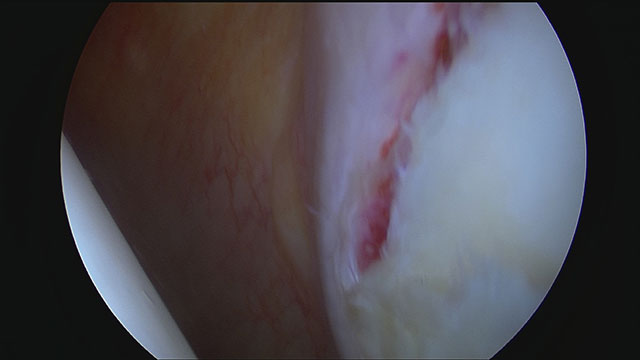

Blick von hinten in die linke Schulter eines Patienten nach Schulterluxation. Im Vordergrund rechts ist die Pfanne. Das Labrum ist abgelöst und die Rissstelle eingeblutet.